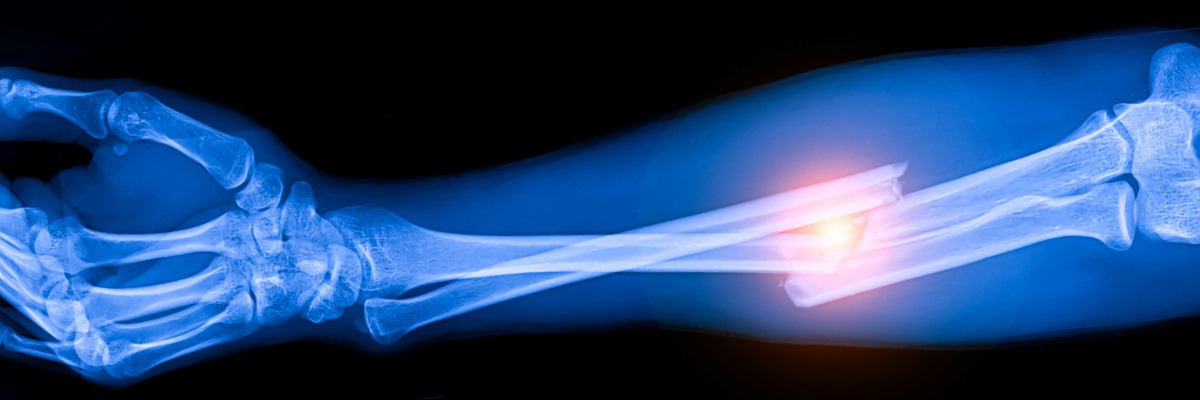

Cuando Carlos Eduardo Villalobos Luzardo, 42 años, ingresó a urgencia tras un accidente en moto, la incertidumbre no estaba solo en cómo reparar sus fracturas, sino en si su pierna podría conservarse. Presentaba fracturas expuestas de tibia y peroné, una de las formas más complejas de trauma ortopédico, donde el daño óseo se combina con compromiso severo de tejidos blandos y alto riesgo de infección, secuelas o amputación.

Casos como este no son excepcionales. A diario, accidentes de tránsito y laborales generan fracturas de alta energía que no solo afectan la movilidad, sino la viabilidad de una extremidad. Frente a este tipo de lesiones, se ha consolidado el enfoque ortoplástico: un modelo que integra desde el inicio a traumatólogos y cirujanos plásticos. “Más que una técnica, es una forma de trabajo que combina tecnología y coordinación. No se trata sólo de ‘unir el hueso’, sino de anticiparse a complicaciones como infecciones, entre otros”, explica Álvaro Zamorano, traumatólogo y jefe del equipo de extremidades inferiores de Mutual de Seguridad.

“Hoy, la tecnología cumple un rol habilitador: se utiliza inteligencia artificial para la planificación preoperatoria, junto con implantes avanzados —como clavos endomedulares con antibióticos— que permiten fijar fracturas complejas reduciendo el riesgo de infección”, señala Vincenzo Giordano, especialista del Hospital Municipal Miguel Couto de Brasil. Advierte, sin embargo, que su efectividad depende de su correcta aplicación: “La mejor tecnología no opera en el vacío; su éxito depende de lograr un equilibrio mecano-biológico”.

Ese equilibrio implica asegurar estabilidad con implantes, respetar la biología de los tejidos y optimizar los tiempos quirúrgicos. Retrasos o decisiones fragmentadas pueden traducirse en infecciones, múltiples cirugías o secuelas permanentes.